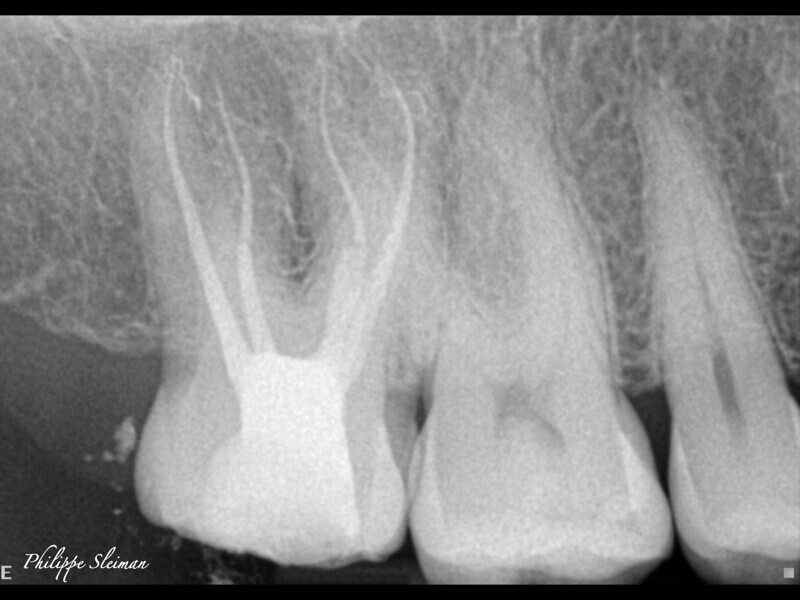

Clinical management of maxillary second molar root canal therapy in different anatomical situations